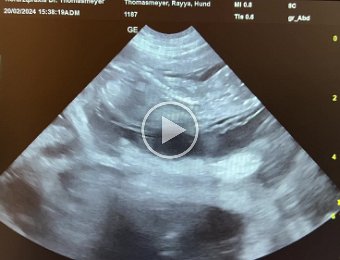

36. Tag

20-24.02.24